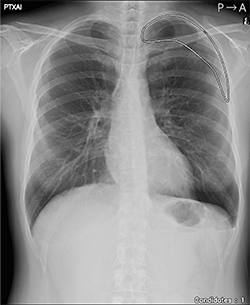

オリジナル画像 |

気胸の検出領域を表示 |